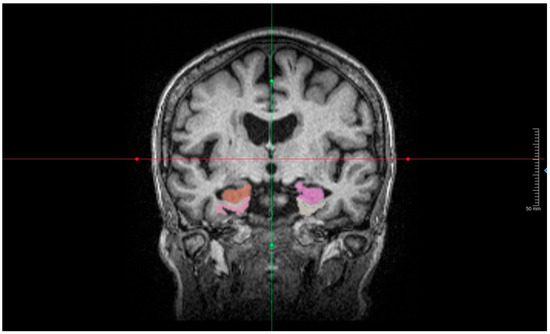

Artificial Intelligence-Assisted Volumetric Brain Analysis Correlated with CSF Biomarkers in Alzheimer’s Disease: A Pilot Study

by Pukovisa Prawiroharjo, Amelia Nur Vidyanti, Yuliarni Syafrita, Reyhan Eddy Yunus, Aldithya Fakhri, Violine Martalia, Aileen Gabrielle, Sarah Alya Rahmayani, Gamael Marcel, Vidya Gani Wijaya and Alya Ayu Tazkia

Diagnostics 2026, 16(7), 1050; https://doi.org/10.3390/diagnostics16071050 - 31 Mar 2026

Background/Objectives: Alzheimer’s disease (AD) is a leading cause of dementia globally, yet standard diagnostic markers like cerebrospinal fluid (CSF) analysis and molecular imaging are invasive and resource-intensive. While artificial intelligence (AI)-based volumetric magnetic resonance imaging (MRI) offers a scalable and non-invasive alternative, [...] Read more.

Background/Objectives: Alzheimer’s disease (AD) is a leading cause of dementia globally, yet standard diagnostic markers like cerebrospinal fluid (CSF) analysis and molecular imaging are invasive and resource-intensive. While artificial intelligence (AI)-based volumetric magnetic resonance imaging (MRI) offers a scalable and non-invasive alternative, data correlating these structural metrics with fluid biomarkers and cognitive status in Southeast Asian populations are scarce. This study addresses this critical gap by examining the within-cohort relationship between CSF biomarkers and regional brain volumes derived from AI-assisted MRI in Indonesian patients with clinically diagnosed AD, providing novel data for an underrepresented population. Methods: Twenty-one AD patients from three national referral hospitals in Indonesia underwent lumbar puncture for CSF biomarker analysis and 3 Tesla structural brain MRI. Brain volumes were analyzed using United Imaging Intelligence software, focusing on AD-relevant regions (hippocampus, entorhinal cortex, parahippocampus, precuneus, and posterior cingulate cortex [PCC]). Results: Spearman’s correlation revealed significant positive associations between CSF Aβ42 levels and several brain regions. Strong correlations were found with the right entorhinal volume indexed to intracranial volume (VICV) (r = 0.601, p = 0.004), right PCC VICV (r = 0.603, p = 0.004), right entorhinal volume (r = 0.533, p = 0.013), and right hippocampus VICV (r = 0.503, p = 0.020). Furthermore, MoCA-InA scores demonstrated highly significant positive correlations with CSF Aβ42 concentrations (r = 0.720, p < 0.001), right Hippocampus VICV (r = 0.703, p < 0.001), and right PCC VICV (r = 0.695, p < 0.001). No significant correlations were found between CSF pTau or the pTau/Aβ42 ratio and regional volumes. Conclusions: These results highlight the entorhinal cortex and PCC as early affected regions where CSF Aβ42 correlates with preserved volume, supporting their role as structural markers in early AD. The absence of pTau associations may reflect early-stage pathology or limitations of cross-sectional volumetry. In resource-limited settings, AI-assisted volumetric MRI demonstrates potential utility as a non-invasive tool for stratifying amyloid-associated brain atrophy and staging disease severity. Full article